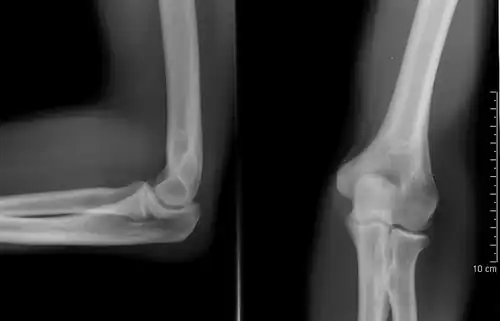

Projectional radiography

The creation of images by exposing an object to X-rays or other high-energy forms of electromagnetic radiation and capturing the resulting remnant beam (or "shadow") as a latent image is known as "projection radiography". The "shadow" may be converted to light using a fluorescent screen, which is then captured on photographic film, it may be captured by a phosphor screen to be "read" later by a laser (CR), or it may directly activate a matrix of solid-state detectors (DR—similar to a very large version of a CCD in a digital camera). Bone and some organs (such as lungs) especially lend themselves to projection radiography. It is a relatively low-cost investigation with a high diagnostic yield. The difference between soft and hard body parts stems mostly from the fact that carbon has a very low X-ray cross section compared to calcium.